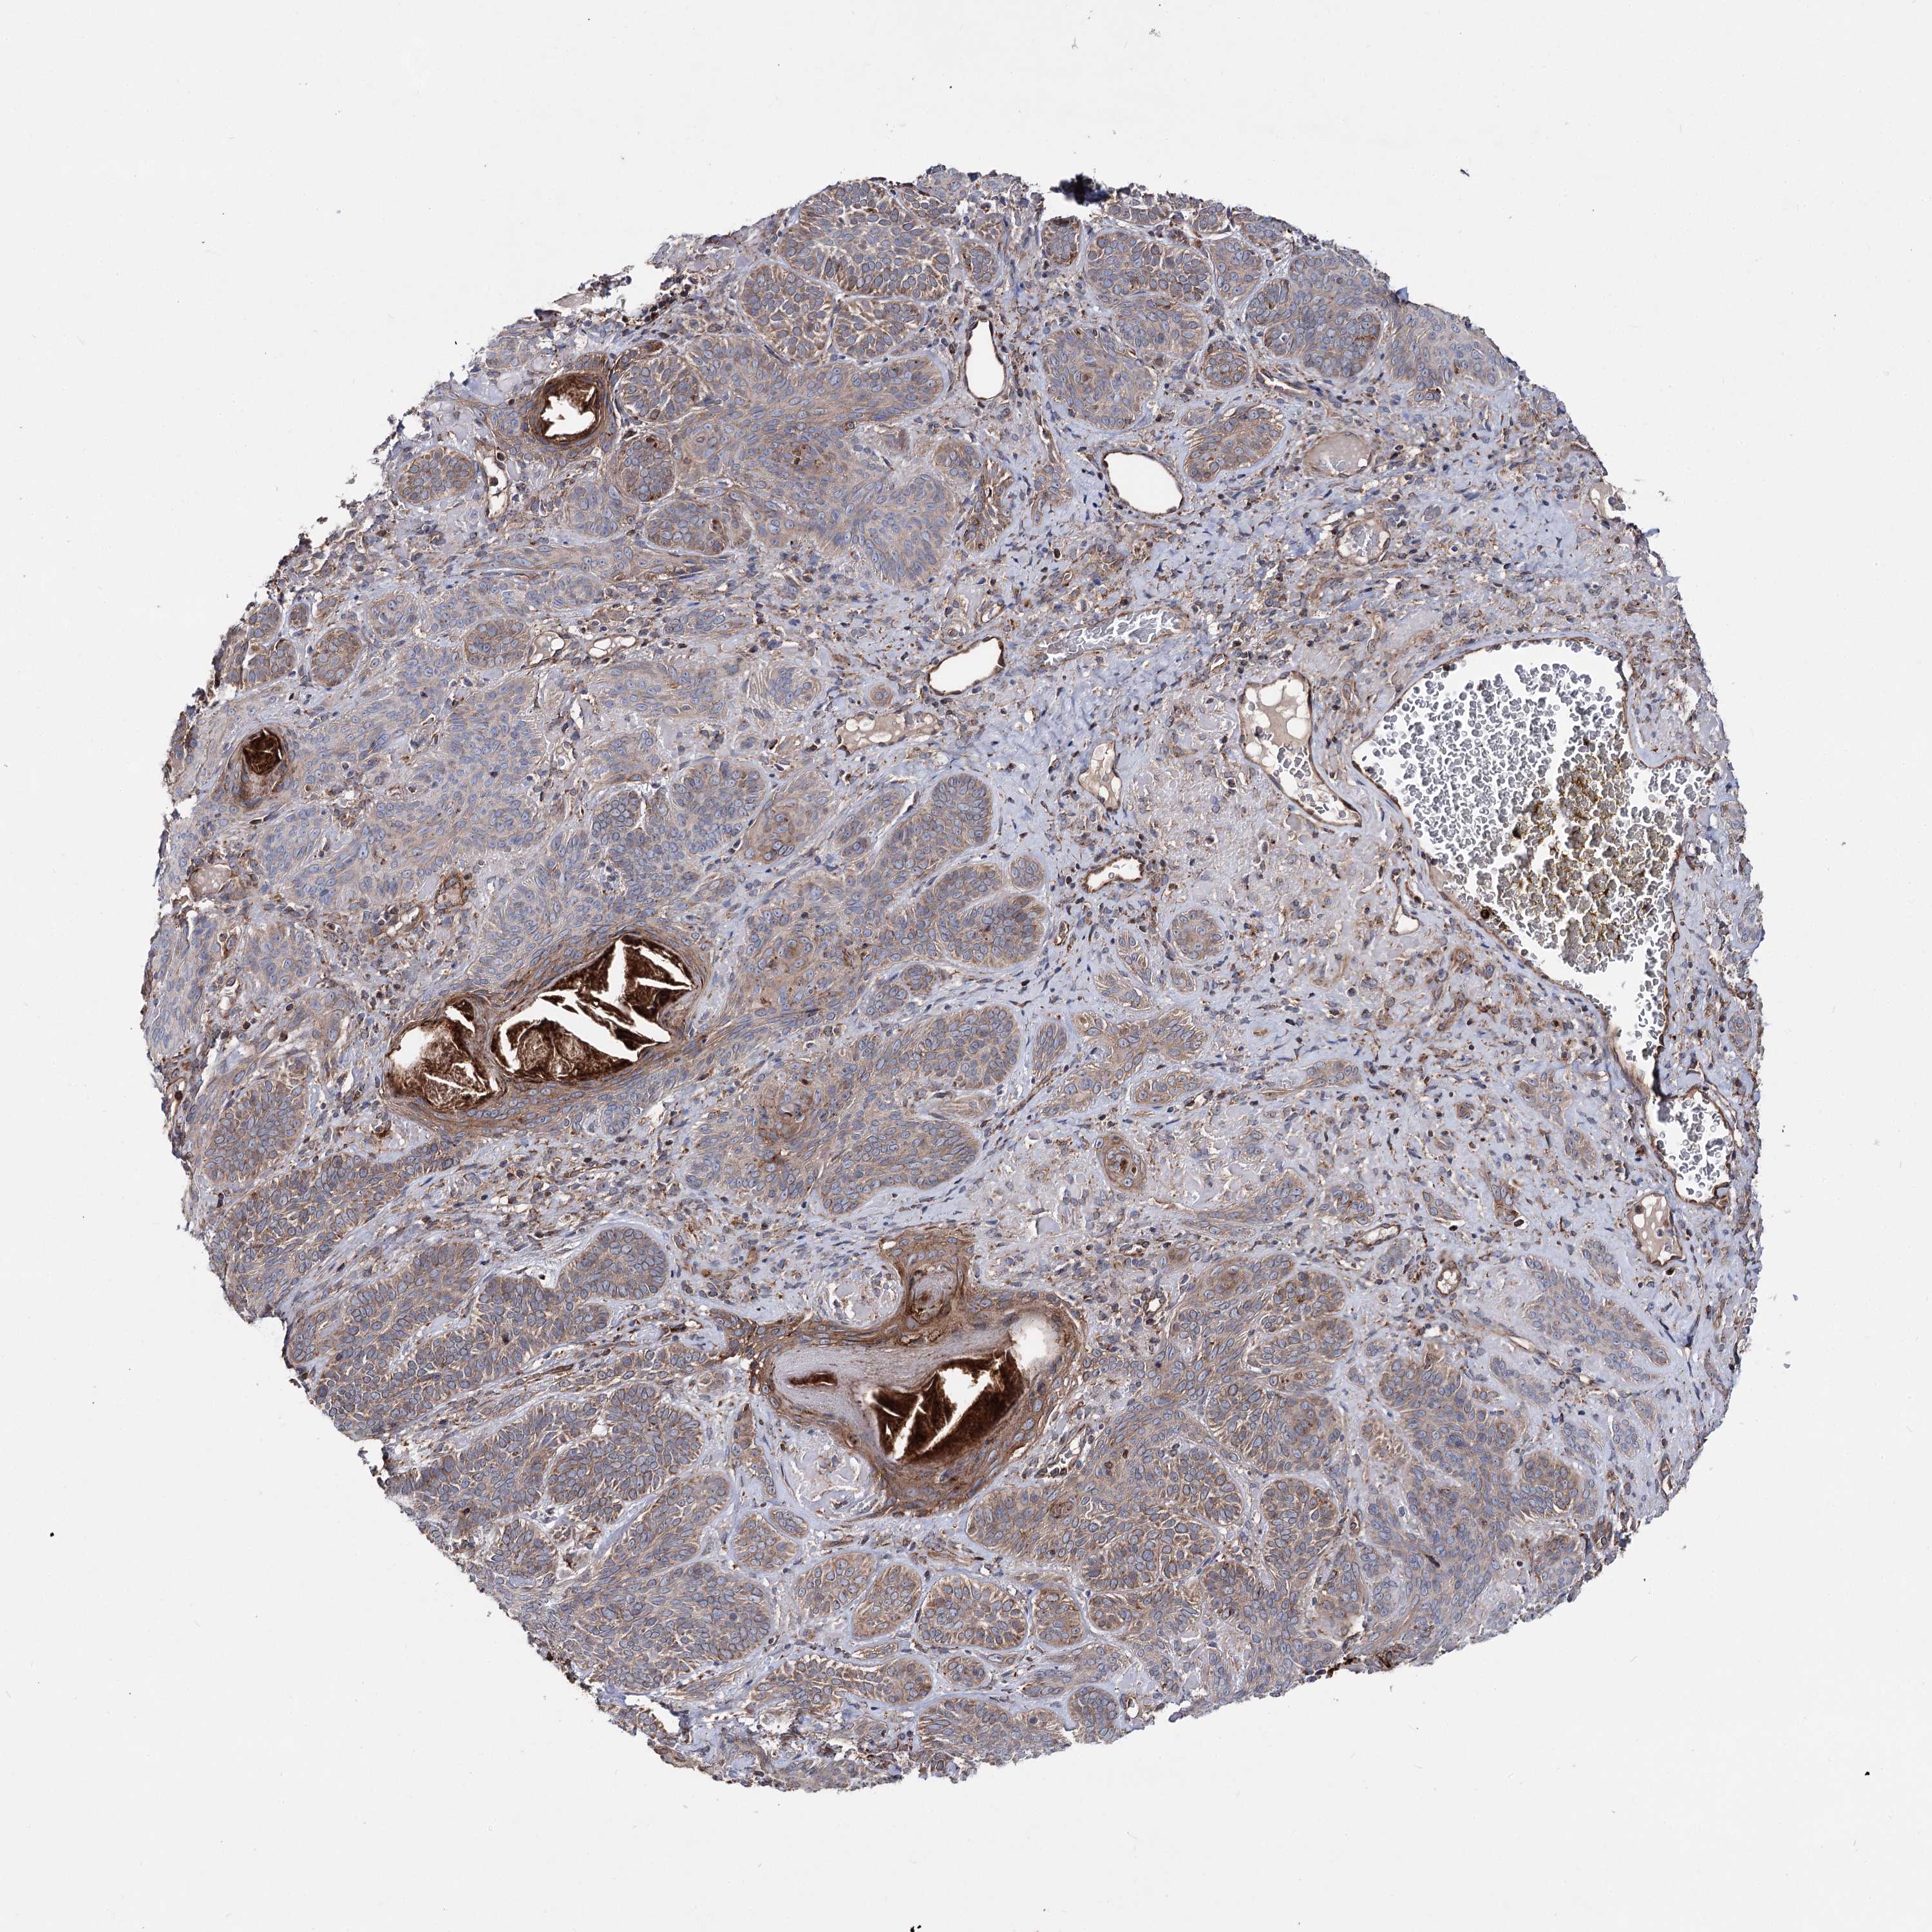

Basal cell and squamous cell cancer

SKIN CANCER - Protein expressioni

A mouse-over function shows sample information and annotation data. Click on an image to view it in a full screen mode. Samples can be filtered based on level of antibody staining by selecting one or several of the following categories: high, medium, low and not detected. The assay and annotation is described here.

Antibody stainingi

Antibody staining in the annotated cell types in the current human tissue is reported as not detected, low, medium, or high, based on conventional immunohistochemistry profiling in selected tissues. This score is based on the combination of the staining intensity and fraction of stained cells.

Each image is clickable and will lead to virtual microscopy that enables deeper exploration of all samples and also displays staining intensity scores, fraction scores and subcellular localization as well as patient and tissue information for each sample.

Antibody HPA038694

Antibody HPA038695

Staining

High

Medium

Low

Not detected

Intensity

Strong

Moderate

Weak

Negative

Quantity

>75%

75%-25%

<25%

None

Location

Nuclear

Cytoplasmic/membranous

Cytoplasmic/membranous,nuclear

Basal cell carcinoma